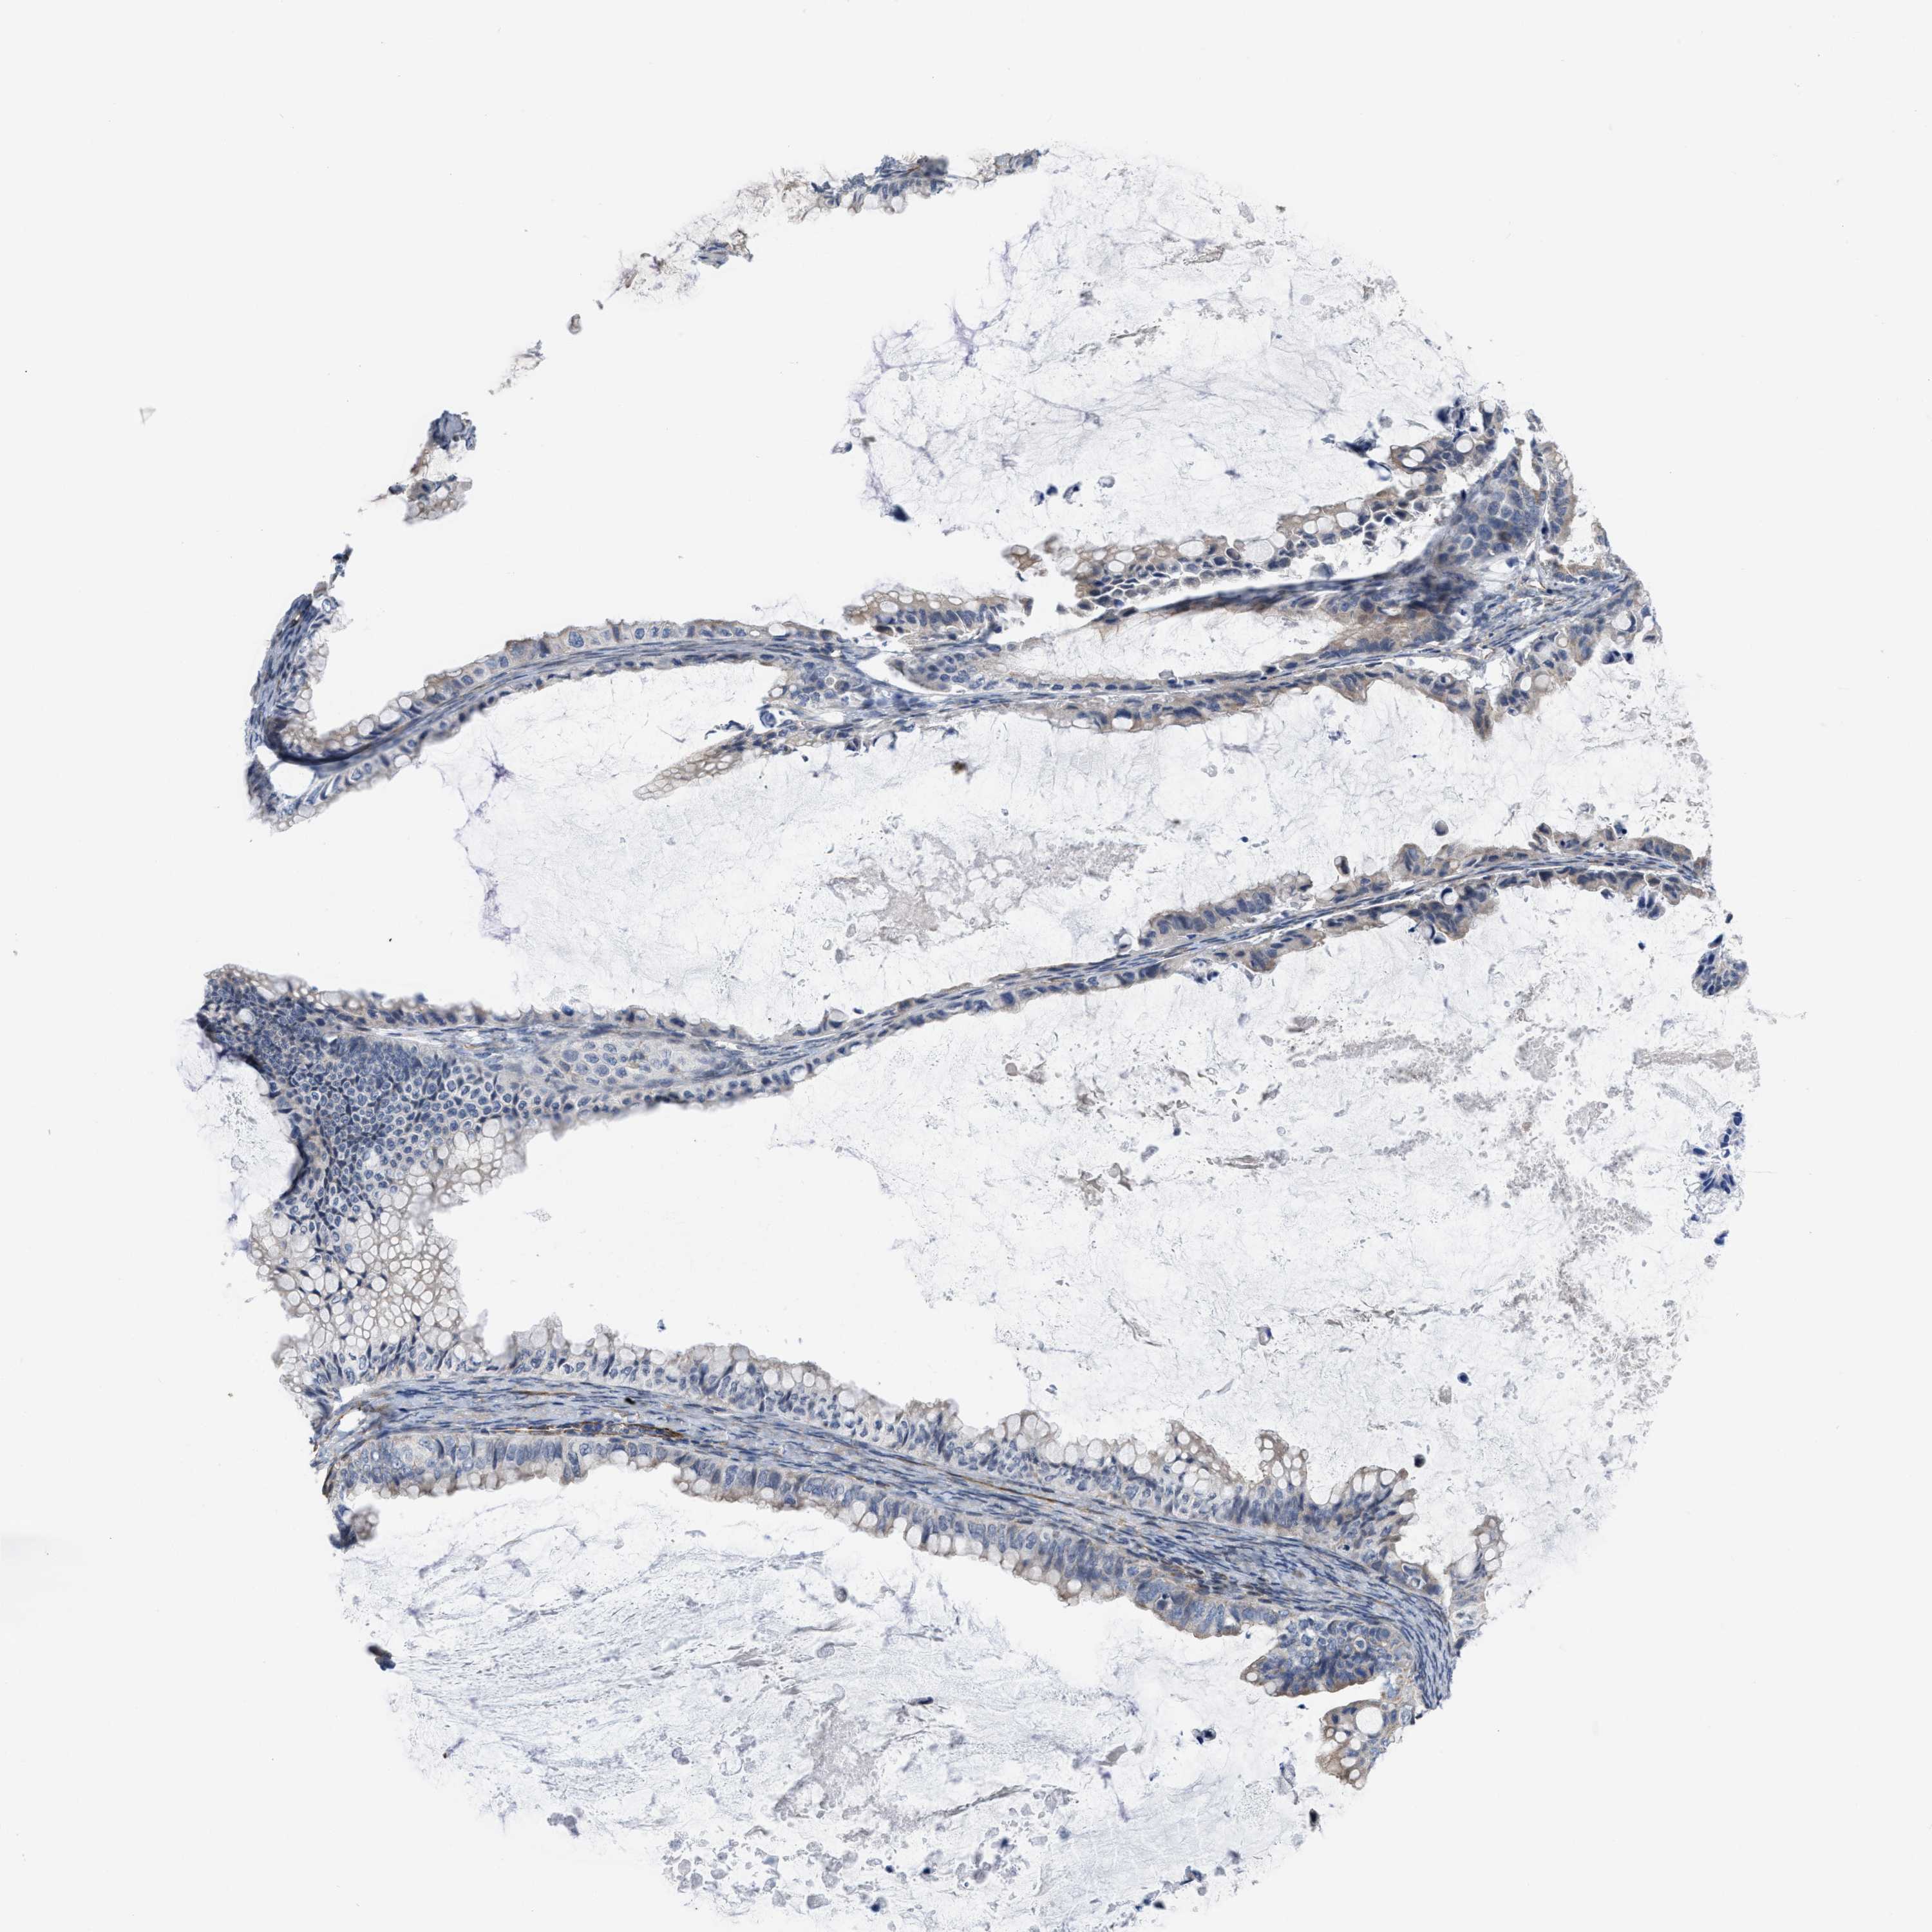

OVARIAN CANCER - Protein expressioni

A mouse-over function shows sample information and annotation data. Click on an image to view it in a full screen mode. Samples can be filtered based on level of antibody staining by selecting one or several of the following categories: high, medium, low and not detected. The assay and annotation is described here.

Note that samples used for immunohistochemistry by the Human Protein Atlas do not correspond to samples in the TCGA dataset.

Antibody stainingi

Antibody staining in the annotated cell types in the current human tissue is reported as not detected, low, medium, or high, based on conventional immunohistochemistry profiling in selected tissues. This score is based on the combination of the staining intensity and fraction of stained cells.

Each image is clickable and will lead to virtual microscopy that enables deeper exploration of all samples and also displays staining intensity scores, fraction scores and subcellular localization as well as patient and tissue information for each sample.

Antibody HPA019460

Staining

High

Medium

Low

Not detected

Intensity

Strong

Moderate

Weak

Negative

Quantity

>75%

75%-25%

<25%

None

Location

Nuclear

Cytoplasmic/membranous

Cytoplasmic/membranous,nuclear

Cystadenocarcinoma, serous, NOS

Carcinoma, endometroid

Cystadenocarcinoma, mucinous, NOS

Carcinoma, NOS